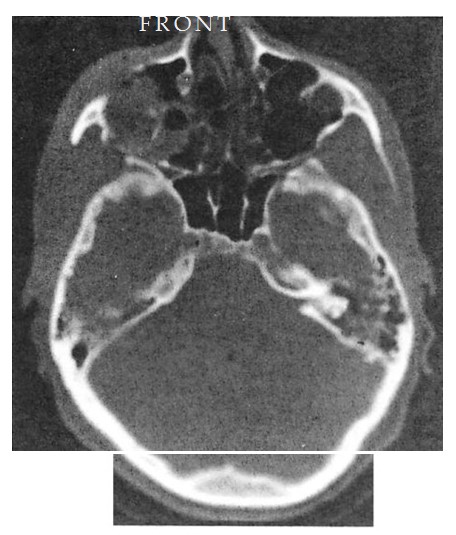

Fig 7. Very high energy Le Fort injury with open crush injury on the left side. Miniplates were used for fixation at maxillary buttresses and zygomaticofrontal sutures. Microplates were used along infraorbital rim and along the zygomatic arch on both sides. Computed tomographic (CT) scan performed 48 hours postoperatively shows loss of infraorbital rim projection on the severely comminuted left side and good projection on less severely injured right side. (A) Preoperative coronal CT shows pronounced lateral displacement of the zygoma on the left side. (B) Preoperative axial CT shows comminution and telescoping of left zygomatic arch. (C) Postoperative CT at 48 hours shows infraorbital rim and malar and arch collapse on left side.